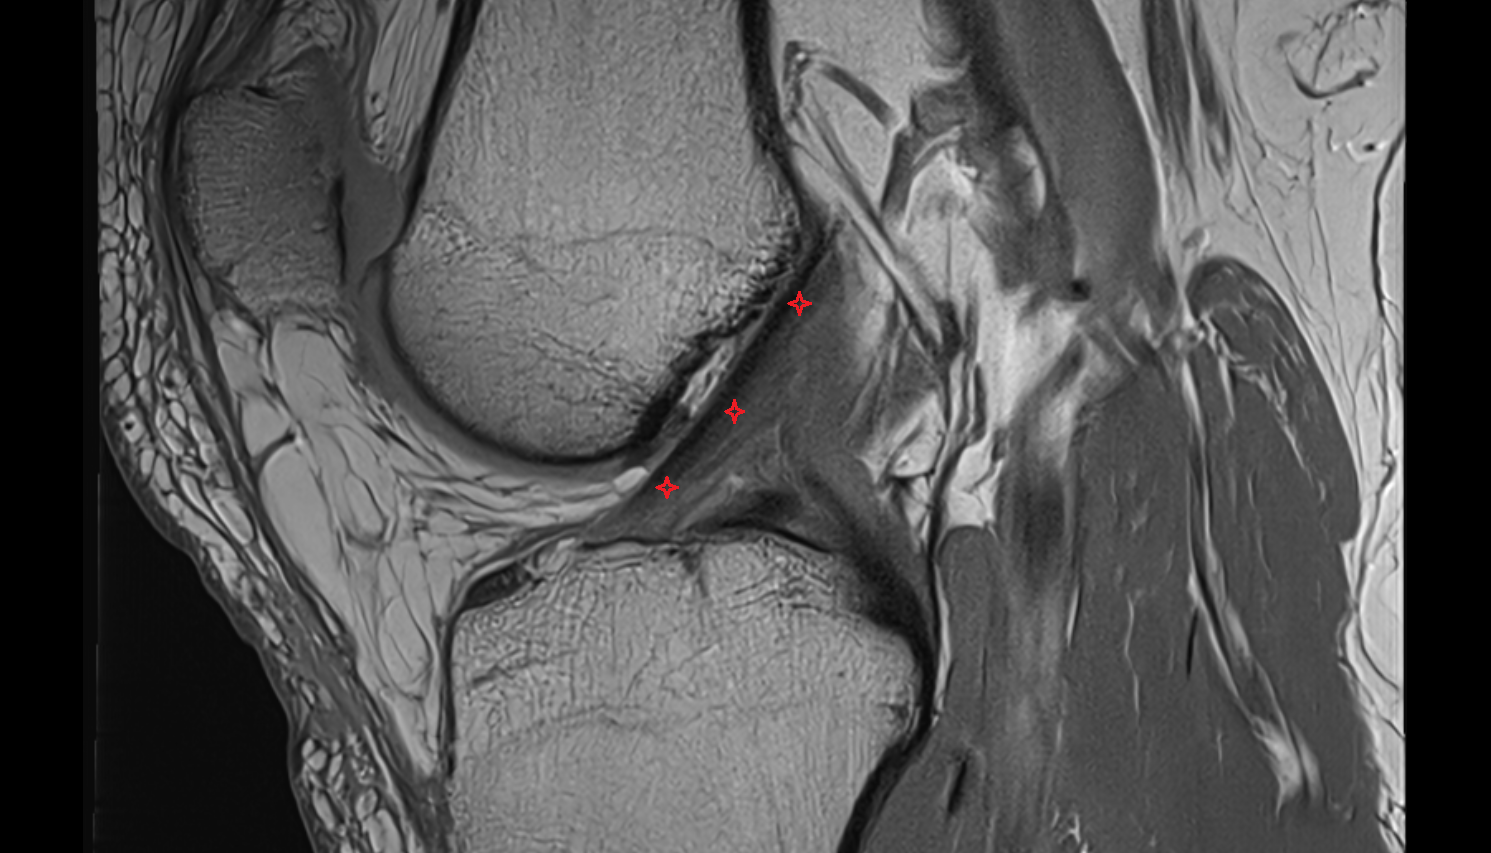

- Anterior cruciate ligament

- Posterior cruciate ligament

- Medial meniscus

- Lateral meniscus